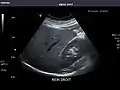

Abdominal Ultrasound (Full Exam)

STRUCTURED REPORT

(Technique: Transabdominal ultrasonography; Device: Toshiba Aplio XG)

Liver: Diffusely homogeneous and normal in echogenicity. No focal mass or contour nodularity. No intrahepatic biliary ductal dilatation.

Portal Vein: Patent main portal vein.

Gallbladder: No stones, wall thickening, or pericholecystic fluid.

Common Bile Duct: Nondilated measuring 1.3 mm at the level of the porta hepatis.

Pancreas: Visualized portions unremarkable.

Spleen: Normal in size.

Kidneys: Right and left kidneys measure 11.5 cm and 12 cm in length respectively. No hydronephrosis. Small left lower pole kidney cyst.

Ascites: None.

Aorta: Visualized portions normal in caliber, 16 x 15 mm.

IVC: Normal.

IMPRESSION:

Normal abdominal ultrasound.